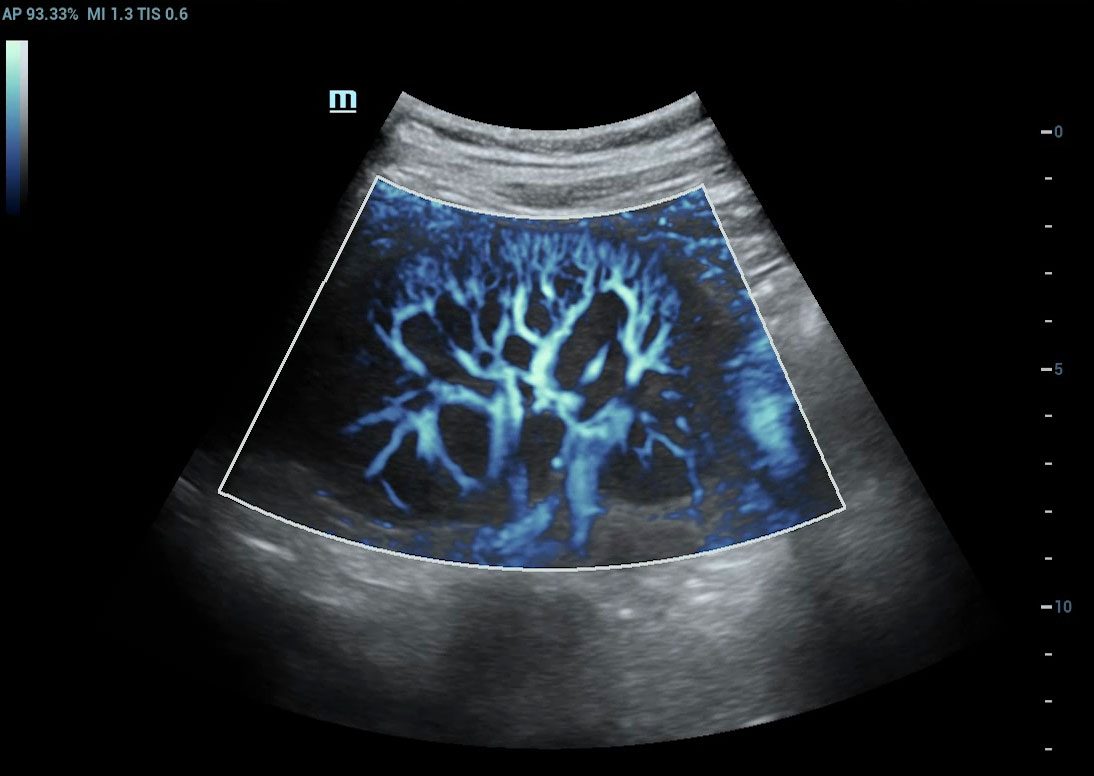

Angiografia ultramicroscû°pica (Ultra Micro Angiography, UMA)

UMA aumenta a confian?a diagnû°stica ao expandir a visibilidade dos fluxos sanguûÙneos atûˋ o nûÙvel de vasos minû¤sculos, com sensibilidade e resolu??o superiores.

sUMA ã Rins

Galeria de imagens

cUMA ã Massa mamûÀria

Massa mamûÀria

Les?es hepûÀticas

sUMA ã Nû°dulos linfûÀticos

sUMA ã Les?o em MSK

UMA ã TestûÙculo

Glazing Flow sUMA em varicocele

CEUS ã Massa mamûÀria

pUMA ã Rim

E Compare ã Massa mamûÀria no L15-3WU

CEUS ã Massa hepûÀtica